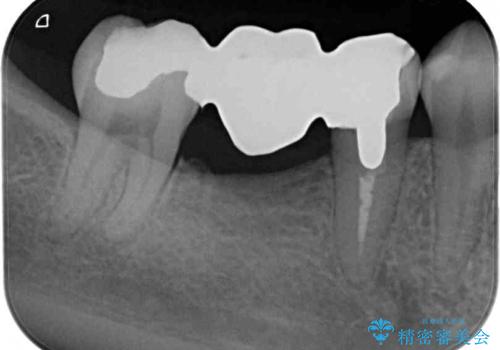

既に抜歯をして歯のない箇所にはインプラント治療をし、ブリッジの土台となっている歯のうち、手前側の小臼歯は既に根管治療をされている歯なのでオールセラミッククラウンへのやり替え、奥側の大臼歯はセラミックインレーへのやり替えをしていくこととしました。

根管治療のやり直しは希望されなかったため、土台の部分からのやり替えです。

患者様の希望、ブリッジの土台となっている歯の状態、インプラントとブリッジの比較などを総合的に判断して、今回のケースではインプラント治療を選択しました。